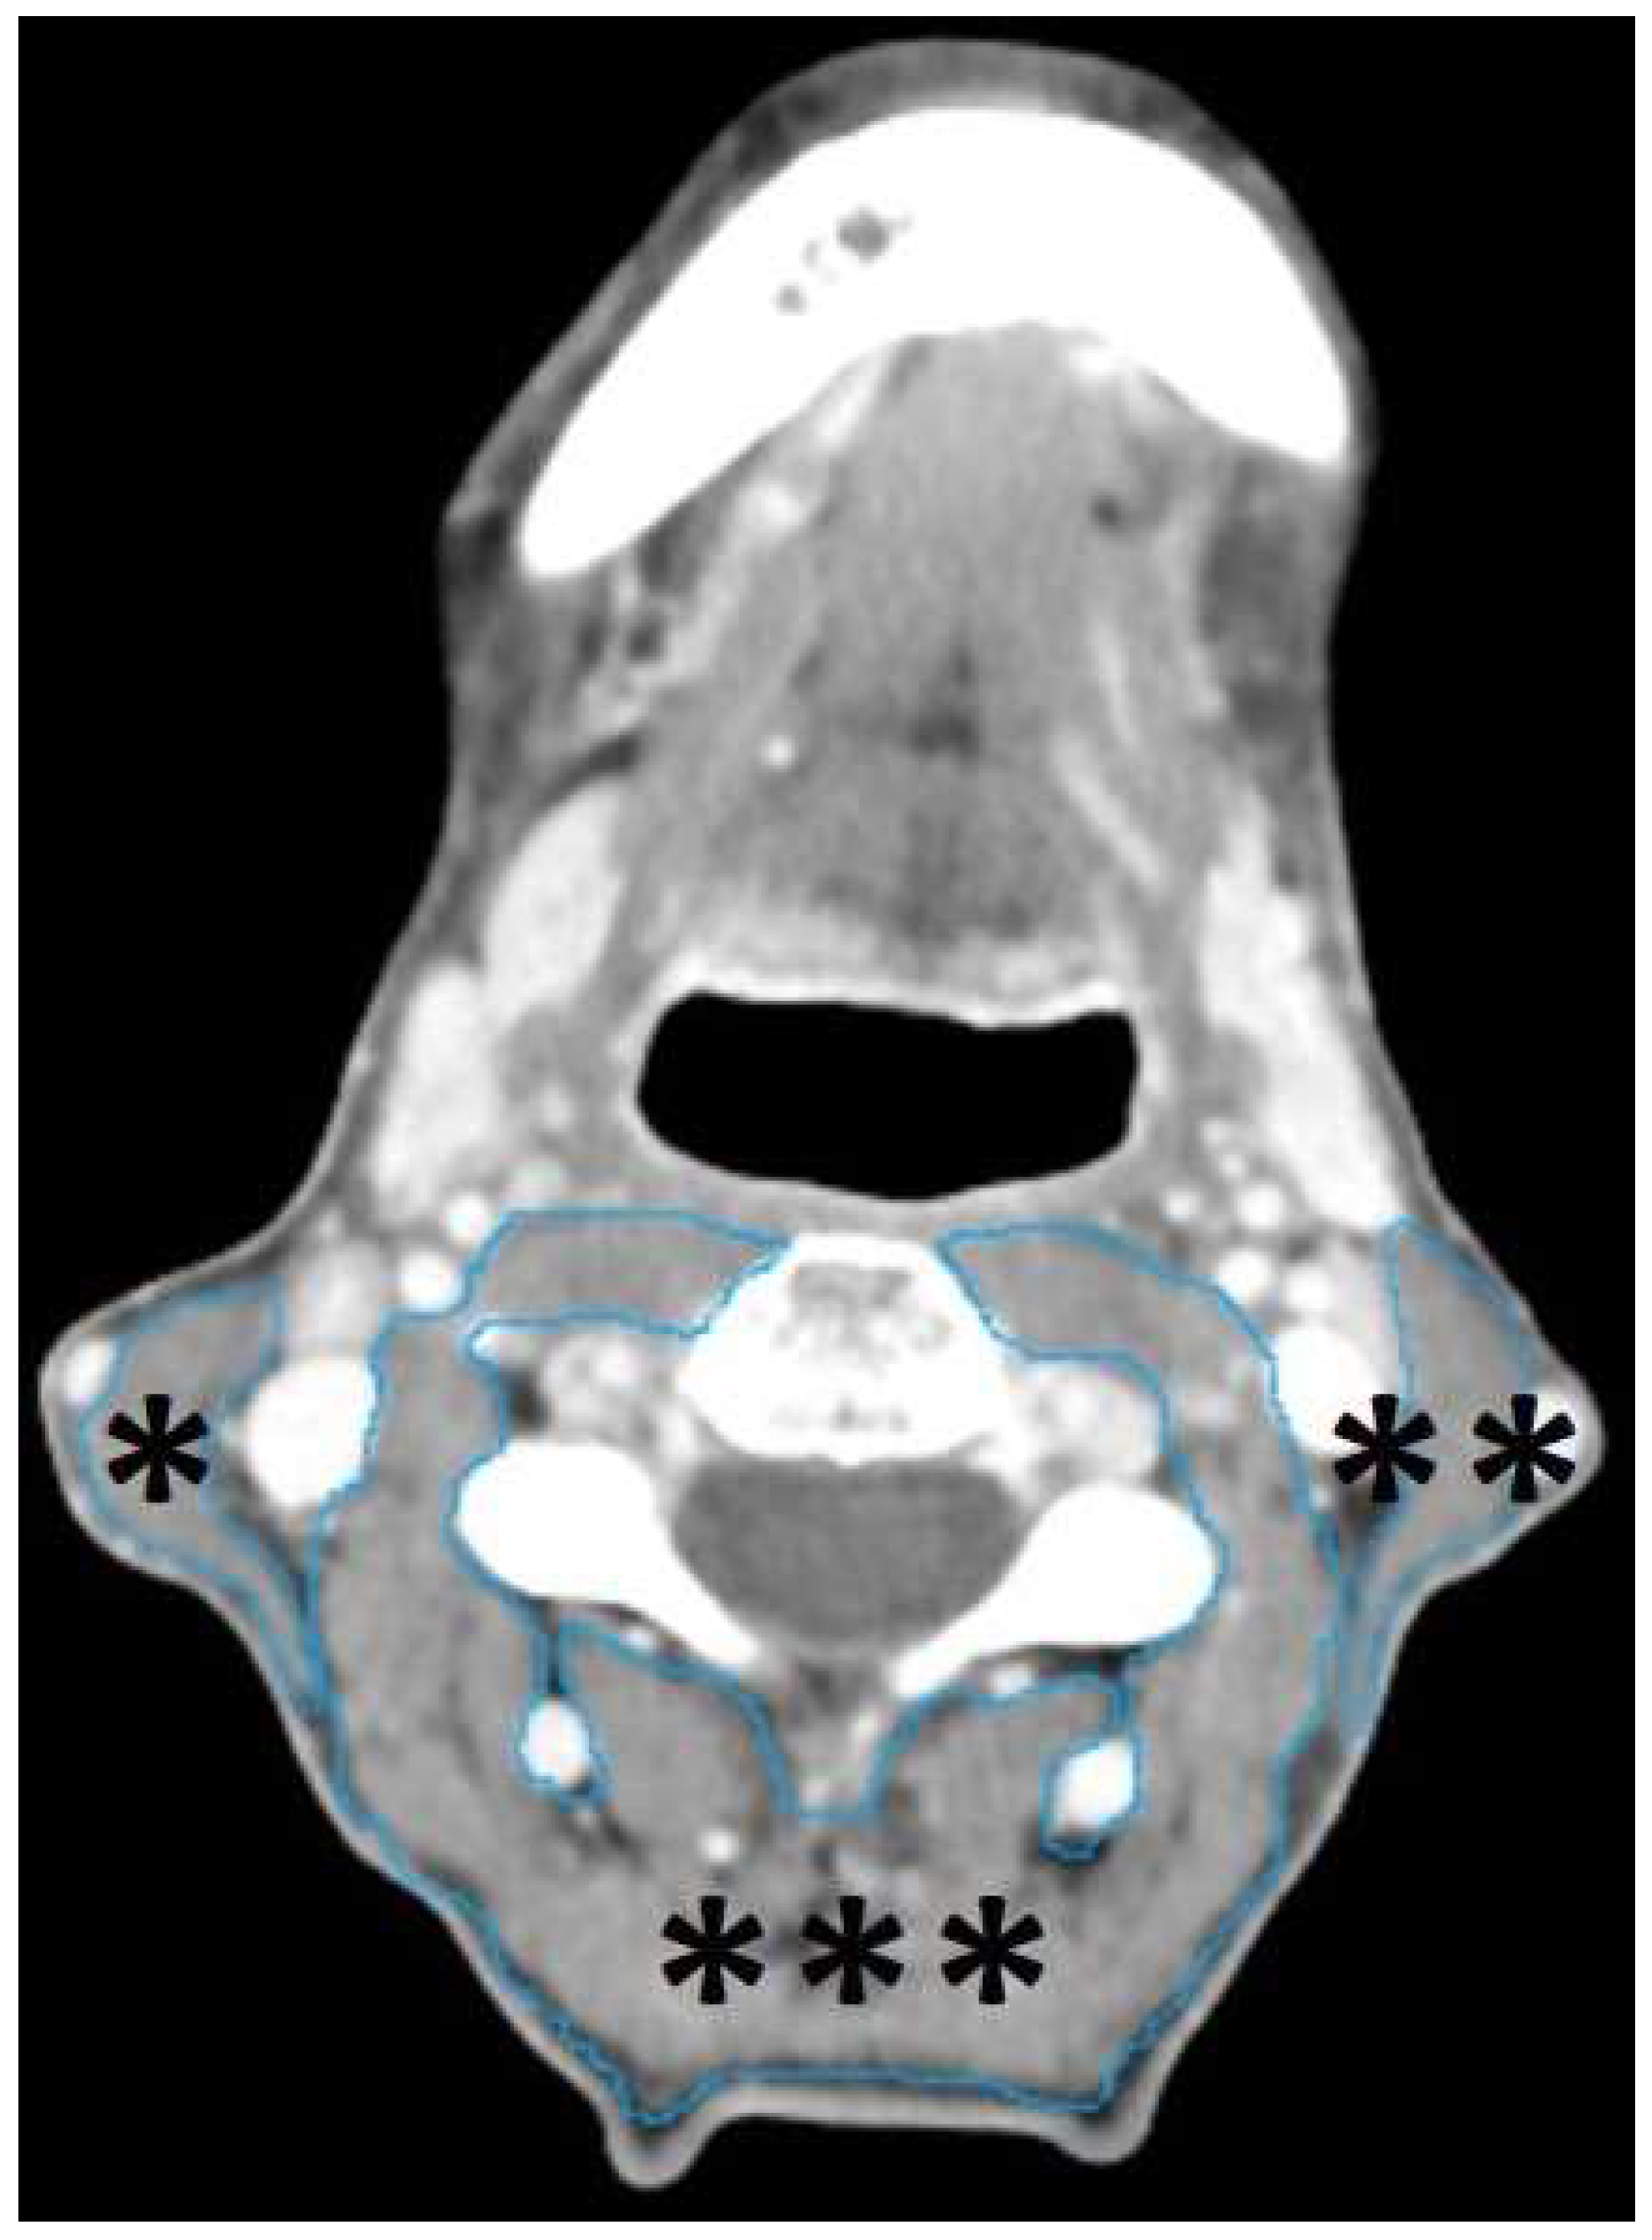

2.4. Segmentation of head-and-neck musculature